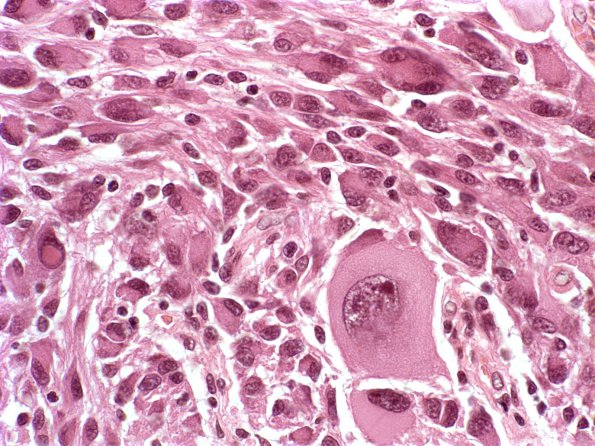

Washington University Experience | NEOPLASMS (NEURONAL) | Ganglioglioma | 18A5 Ganglioglioma (Case 18) H&E 1

This tumor is rich in ganglion neurons of various sizes and numbers of neurons and contains a significant inflammatory infiltrate. (H&E)